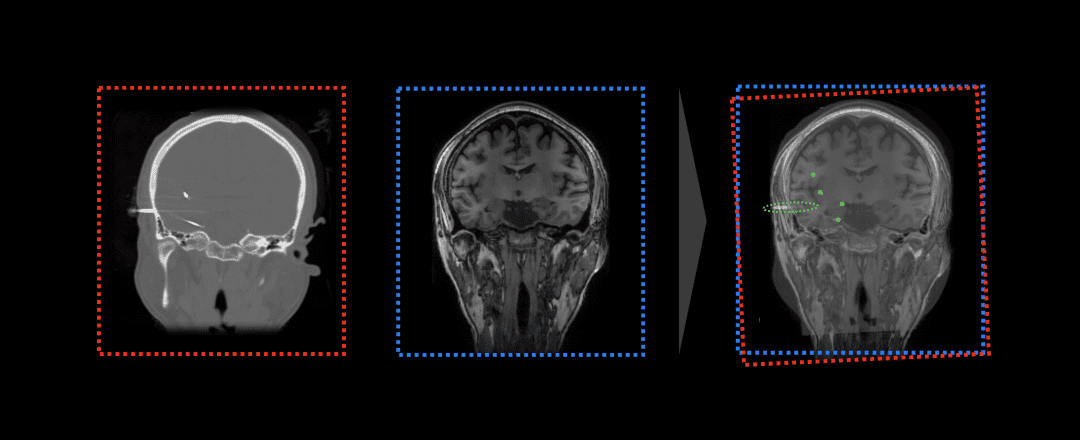

Stereoelectroencephalography (SEEG) technology achieves precise localization of epileptic foci by measuring epileptic discharges through intracranial electrode implantation, providing reference for subsequent radiofrequency thermocoagulation therapy or minimally invasive surgical resection. This technology combines magnetic resonance (MR) and CT imaging examinations to mark abnormal discharges and epileptic seizures recorded by intracranial electrodes, locate epileptic foci, and provide precise evidence for preoperative evaluation. To determine the coordinate positions of SEEG electrodes in the cranium, traditional procedures require doctors to semi-automatically calibrate electrode positions, which is time-consuming and tedious. EEG-X reduces doctor operation time to minutes by integrating automated image registration and electrode calibration, significantly reducing clinical workload and improving accuracy.